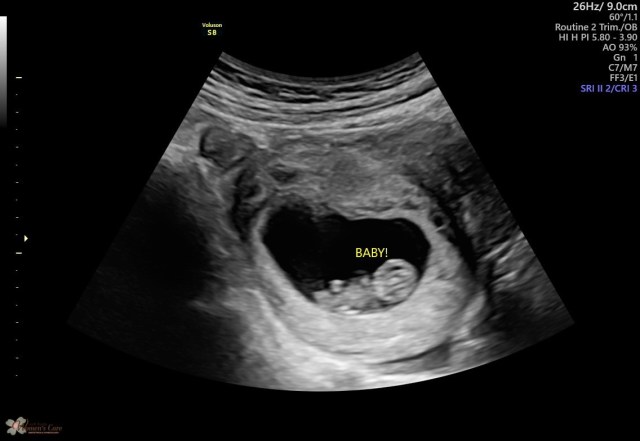

Here are some pregnancy related pictures and videos (including the one where Pfeiffer’s and I told Jeff about the baby!). Sharing changing body pics doesn’t come naturally to me but I feel it’s part of the process and something that should be shared (and I did it last time).